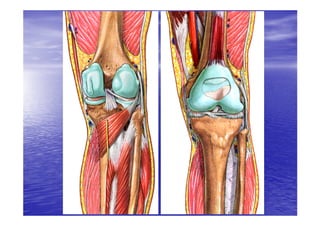

• Le genou est une

grosse articulation

superficielle,

superficielle, il relie

la cuisse et la jambe.

• C’est une articulation

portante,

portante, munie d’un

dispositif ligamentaire

et tendineux lui

assurant la stabilité

nécessaire à la

station debout et

lors de la marche.

marche.

• Le genou est composé de deux articulations

indissociables anatomiquement et

fonctionnellement, elles sont contenues dans la

même capsule articulaire .